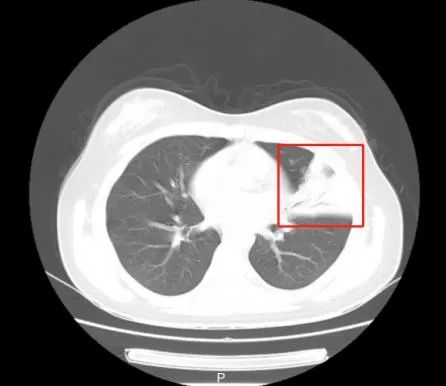

这下,安安的家长急坏了,带着孩子来到浙江省立同德医院儿科就诊,拍了胸部CT显示,左侧肺炎(见下图),正常应该显示黑色为主的部分都白了,是变得很厉害。

儿科医生看过CT后,立即给孩子安排了住院治疗,入院以后完善相关病原检测,发现肺炎支原体检测阳性,导致肺炎的“元凶”很可能就是它。 医生接下来仔细询问安安的发病经过,结合流行病学史及其他检测结果,最终确定肺炎是由肺炎支原体引起 。经过医生们针对性的治疗后,安安的病情也逐渐好转。